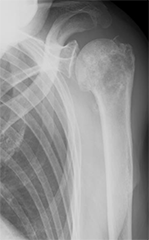

上腕骨腫瘍に対し、広範切除術と腓骨移植術を行った。